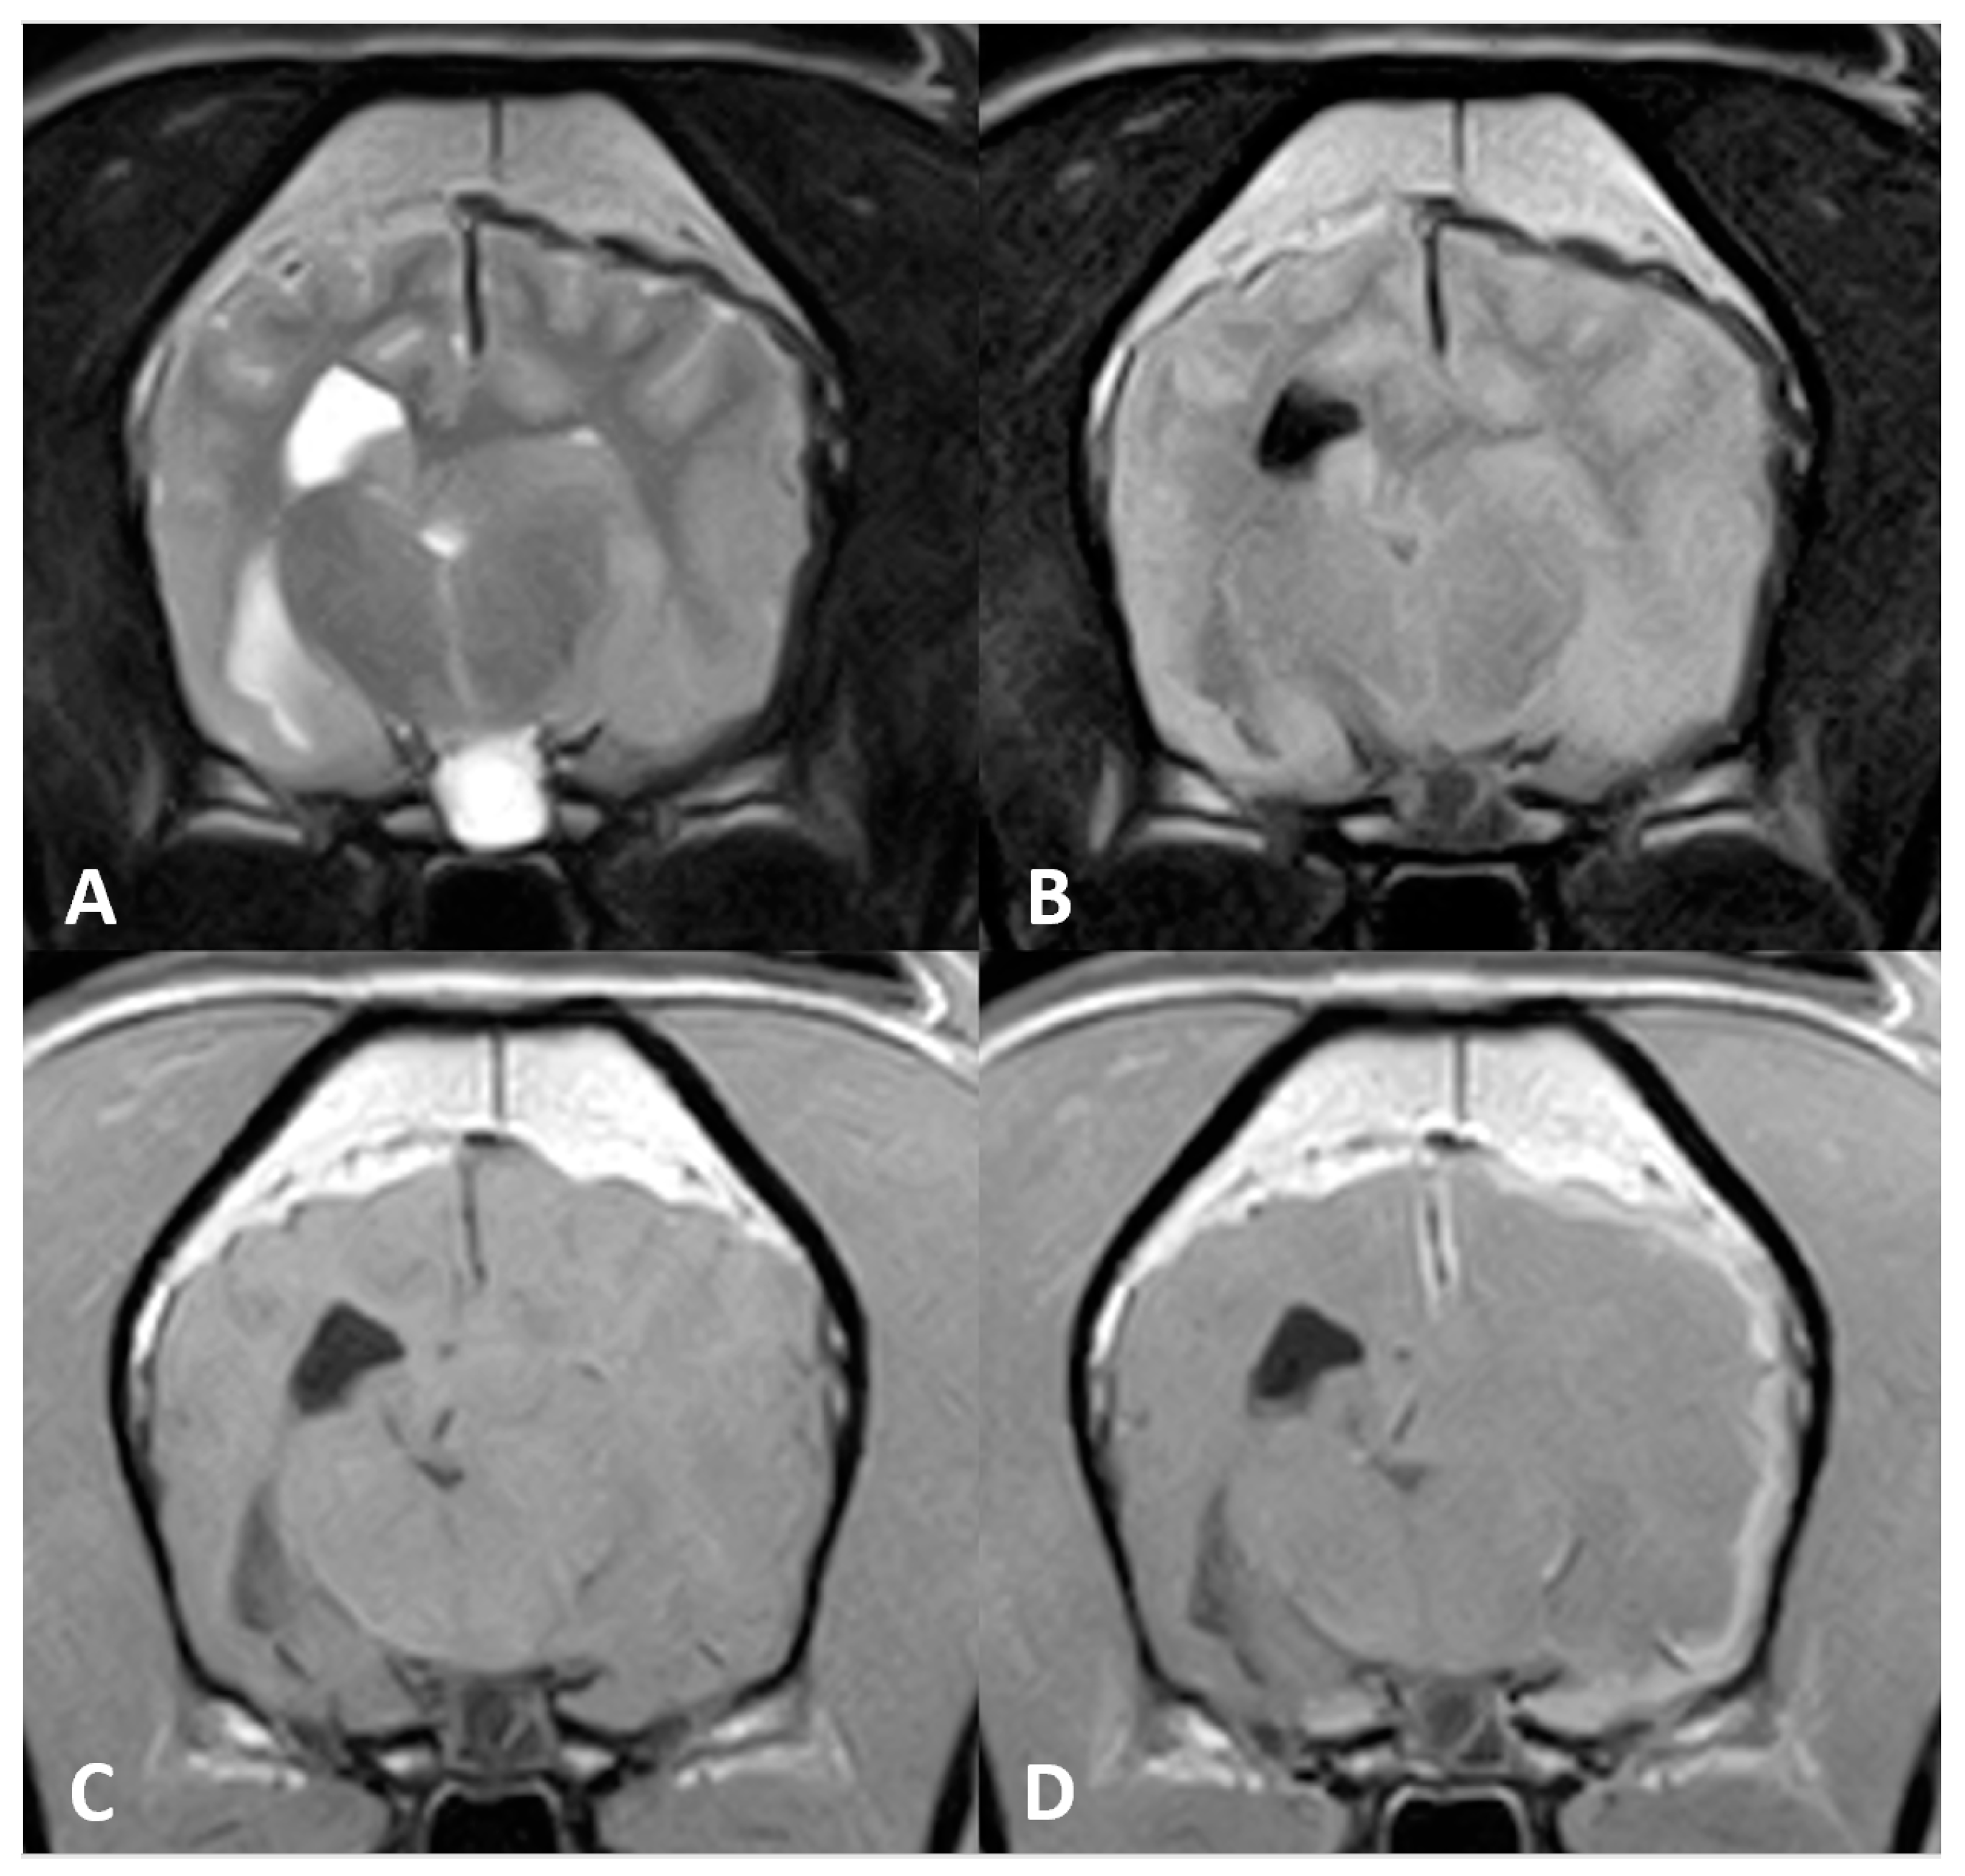

A brain MR imaging study was performed following the same brain protocol as that in Case 1 (see Figure 2), and additional transverse diffusion weighted imaging (DWI) sequences were produced. MR images revealed an extra-axial mass of ill-defined margins that extended from the left olfactory bulb throughout the left frontal and temporal regions and affected the falx cerebri. The mass was hypointense on T2w and hyperintense on T1w images, and exhibited marked homogeneous contrast enhancement. Adjacent to the mass, a second lesion could be distinguished affecting the brain parenchyma over the frontal and temporal left cortices. This lesion was hyperintense on T2w and FLAIR, with focal areas of hypointensity on T1w and several signal voids on T2* that were indicative of intraparenchymal haemorrhage surrounding the mass. A severe mass effect could be identified causing a midline shift to the right side (subfalcine herniation) and a total occlusion of the rostral part of the left lateral ventricle. Moreover, the cerebral sulci were diffusely attenuated and mild transtentorial herniation was appreciated, indicating increased intracranial pressure. No evidence of foraminal herniation was detected.

Figure 2. MR imaging of the brain of Case 2. (A) Transverse images at the level of the frontal lobes on T2w, (B) gradient echo sequences (T2*), (C) T1w and (D) T1w postcontrast (T1w+c). An extra-axial mass is seen in the left frontal cortex, hypointense on T2w images. There were gradient echo signal voids adjacent to the mass, compatible with intraparenchymal bleeds. Note the marked enhancement after contrast administration.